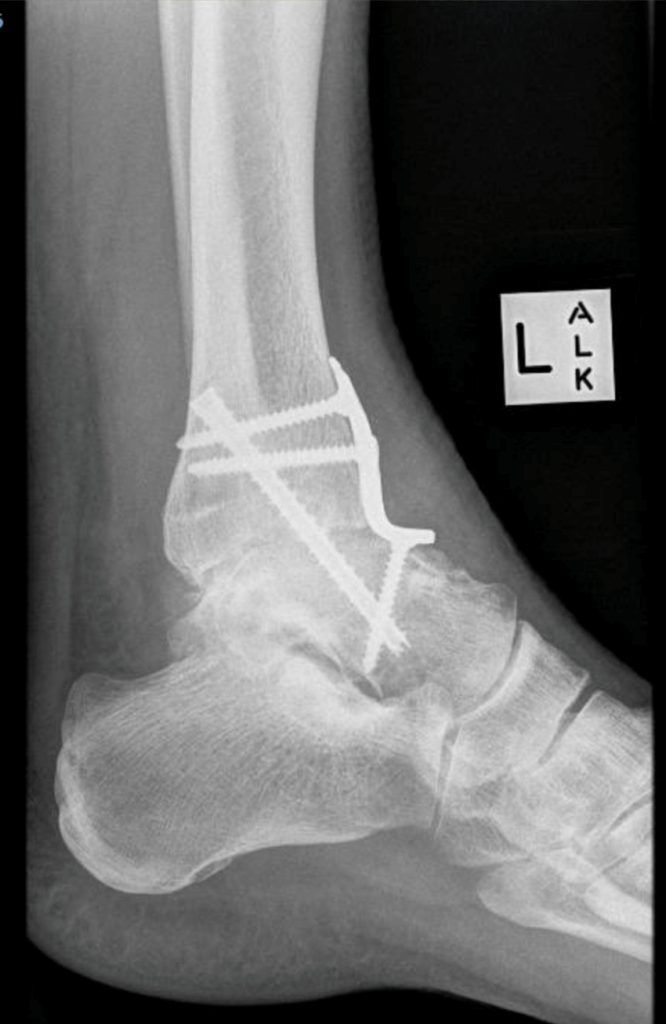

Ankle Arthrodesis

This has been the “gold standard” treatment for severe arthritis. The surgical technique involves removing bone from the tibia and talus and holding them together with screws and or plates. Eventually, the ends of the bones grow or fuse together. Even though ankle motion is eliminated, adjacent joints compensate and may allow up to 30% of this motion to return. However the increased load across these other joints can cause arthritis to develop and up to 10% of patients will require fusion of other joints at some stage in the future.

In the past, this procedure was performed through large incisions. In most cases this can now be carried out using an arthroscopic technique or small incisions in most cases. This results in less pain and a more rapid recovery. In more deformed ankles or following previous surgery, an open technique may still be necessary.